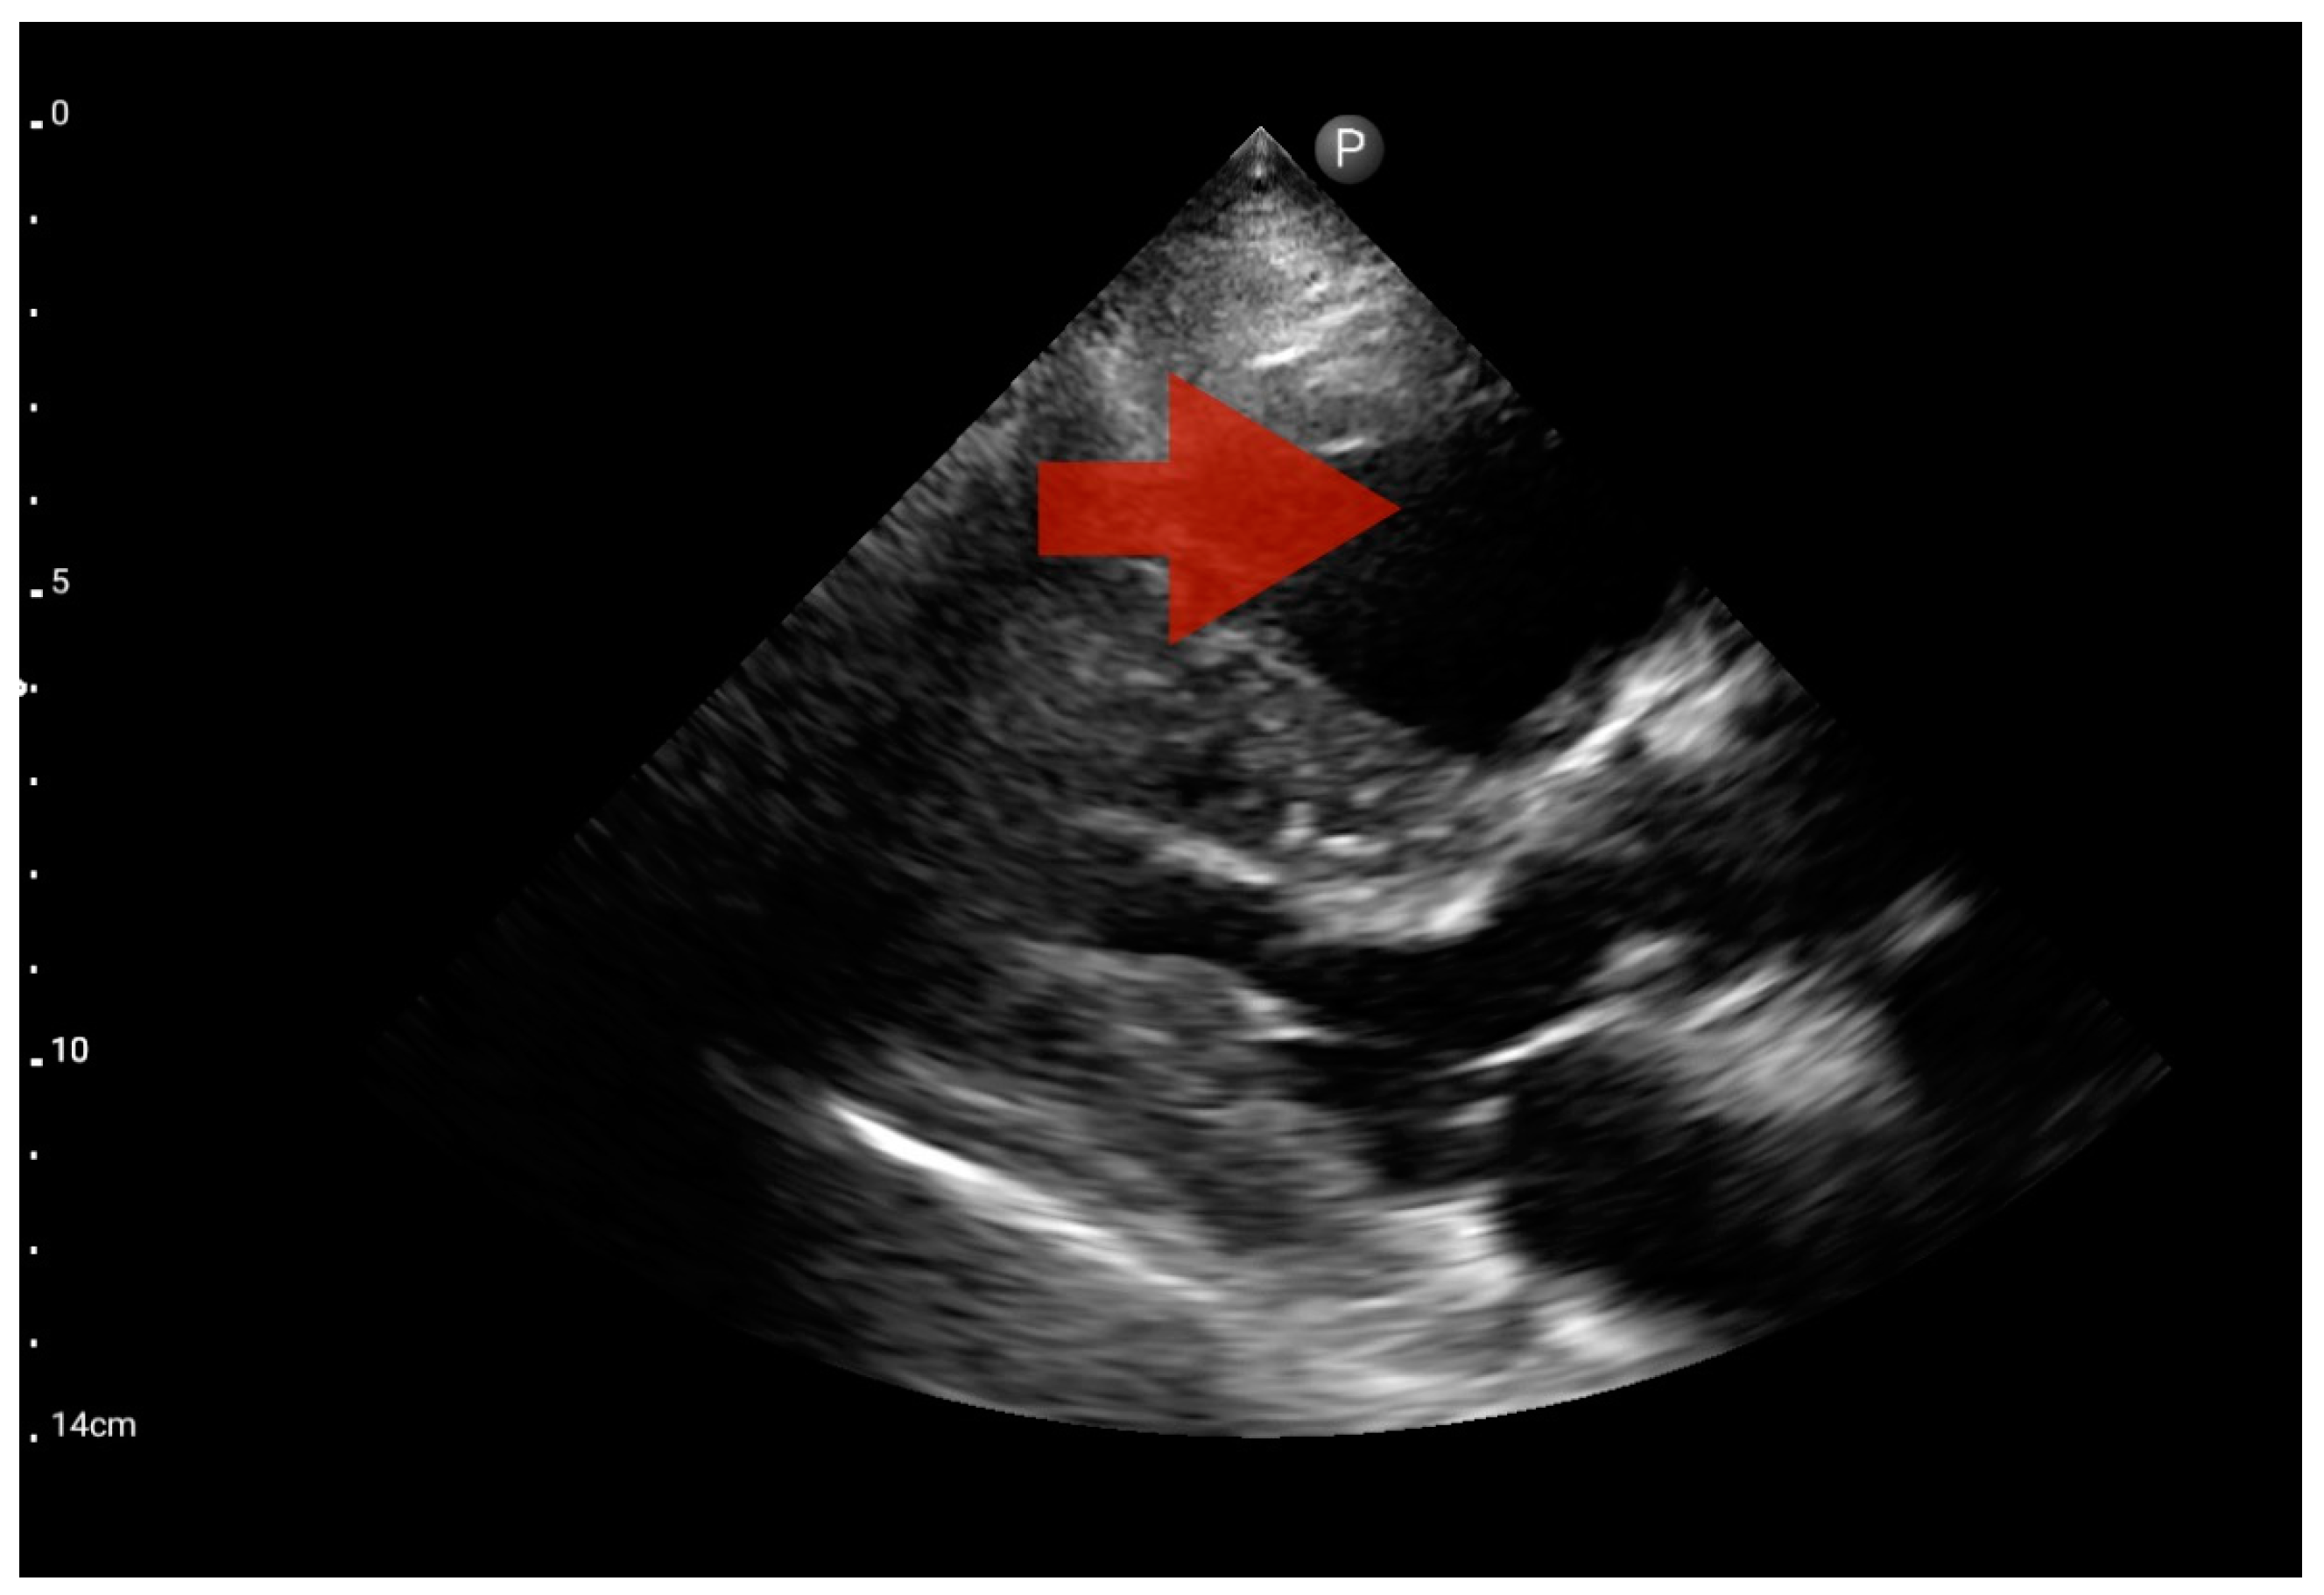

Other detected pathologies, including left ventricle enlargement (2 patients; 12.5%) (Figure 12), right ventricle enlargement (2 patients; 12.5%) (Figure 13) and pericardial effusion (1 patient; 6.25%) (Figure 14), were observed only incidentally. Therefore, further validation in a larger-scale study is warranted to analyze the significance of these symptoms in the pre-hospital setting.

Figure 13.

Right ventricle enlargement; position: parasternal long axis (FATE protocol). Sector probe; the right ventricle is marked with the red arrow, and a significant enlargement of the right ventricle is visible, with a shift of the interventricular septum towards the left ventricle, and an ultrasound picture suggesting pulmonary embolism (source: author’s material—DK).